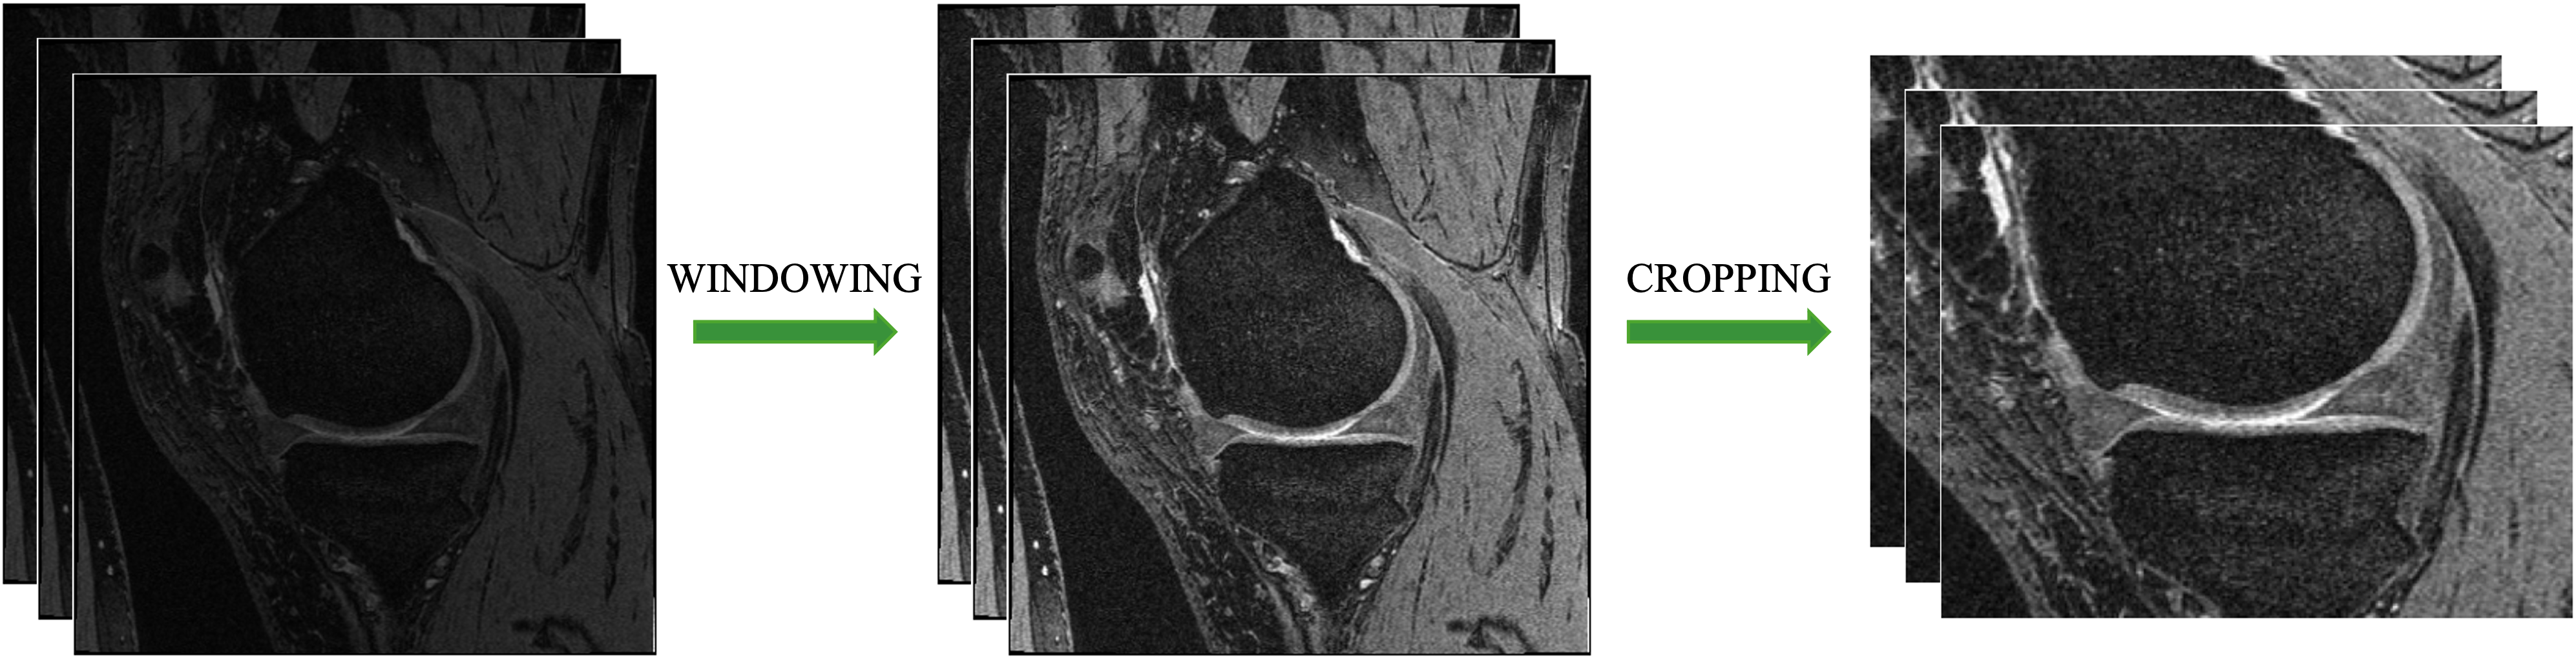

Before training, windowing was performed on the MRI images, clipping the values to between 0 and 0.005, which were then re-scaled between 0 and 1. This clipping window was selected after viewing the intensity distribution in the images. Clipping the intensity range allowed for greater relative contrast between different artifacts in the joint after re-scaling (Fig. 1). The images were then cropped from 384×384×160384384160384\times 384\times 160384 × 384 × 160 down to 200×256×160200256160200\times 256\times 160200 × 256 × 160. The cropped region was selected so that all train/validation meniscus masks fell within it, with an extra margin of safety (20similar-toabsent20\sim 20∼ 20 voxels) given in all directions. Cropping resulted in the menisci taking up a larger volume of the image, as well as reducing the computational memory requirements of model training. The test images were cropped in the same way.

Figure 1: Preprocessing steps performed on the MR Images before model training. Windowing was performed between 0 and 0.005. The cropped region was selected based on the variation in location of ground truths in the train and validation sets.